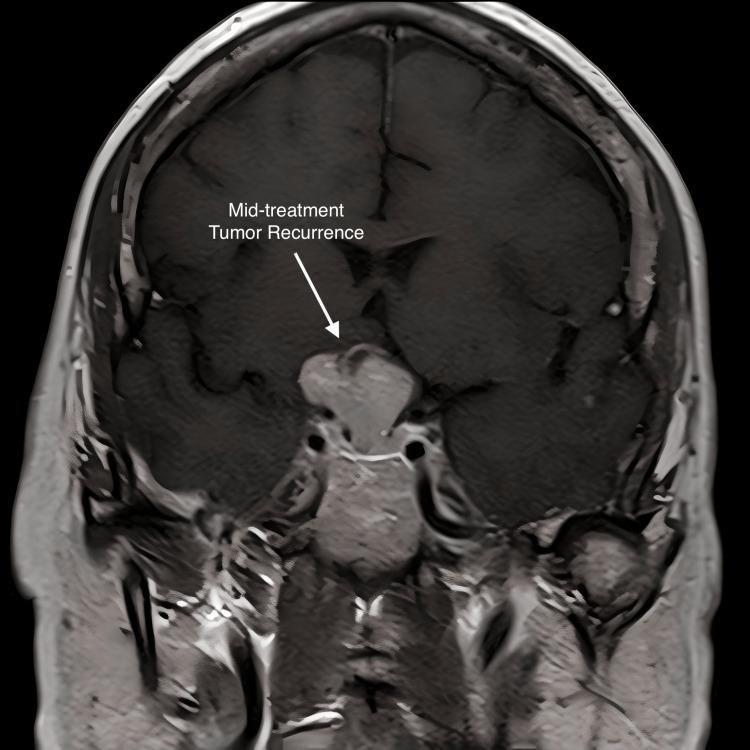

Craniopharyngiomas are rare epithelial malformations in the sellar or suprasellar regions of the craniopharyngeal ducts. Complete surgical resection is difficult due to the location of the base of the skull and the risk of injury to vital neurological structures. Fractionated radiation is effective in controlling residual tumors, but craniopharyngiomas can progress during treatment. The papillary subtype is driven by BRAF V600E mutations. Treatment with BRAF and MEK inhibitors alone has a response rate of 90% but a median progression-free survival of only 12 months. A 57-year-old female presented in May 2017 with complaints of headaches and blurriness in her right eye. Brain MRI demonstrated a 2 cm suprasellar mass engulfing the right optic nerve and optic chiasm. The patient underwent a transsphenoidal hypophysectomy with pathology consistent with a benign pituitary adenoma. Follow-up imaging in August, however, showed recurrence, and a re-resection was performed which surprisingly demonstrated papillary craniopharyngioma. Due to subtotal resection, the patient elected to proceed with intensity-modulated radiation therapy (IMRT) to the tumor bed in April of 2018 with an intended dose of 5400 cGy. After treatment with 2160 cGy in 12 fractions, the patient experienced visual deterioration and progression of the cystic tumor. The patient underwent another debulking procedure but due to rapid recurrence, an endoscopic transsphenoidal fenestration was performed. On postoperative imaging, a cystic mass was still engulfing the right optic nerve and chiasm. Due to the extended break and limited radiation tolerance of the optic chiasm, we elected to re-treat the tumor with an additional 3780 cGy IMRT in conjunction with one cycle of Taflinar and Mekinist, which was completed in August 2018. The cumulative dose to the optic chiasm was 5940 cGy.The patient had an excellent clinical response to treatment with the improvement of vision in her right eye. A brain MRI on 3/29/2019 demonstrated no residual craniopharyngioma. Four-year follow-on CT scan showed no evidence of tumor recurrence. The patient had preservation of vision and did not suffer any late neurological toxicity or new endocrine deficiency. Surgical resection and radiation were ineffective at treating our patient's craniopharyngioma due to rapid cystic progression. This is the first case report in the literature detailing concurrent radiation therapy with BRAF and MEK inhibitors for papillary craniopharyngioma. Despite a suboptimal dose of radiation, our patient had no tumor recurrence and no late toxicity four years after treatment. This represents a potentially novel treatment strategy in this challenging entity.

颅咽管瘤是颅咽管蝶鞍区或鞍上区罕见的上皮性畸形。由于颅底位置以及损伤重要神经结构的风险,完整手术切除困难。分次放疗对控制残留肿瘤有效,但颅咽管瘤在治疗过程中可能进展。乳头状亚型由BRAF V600E突变驱动。单独使用BRAF和MEK抑制剂治疗的缓解率为90%,但无进展生存期的中位数仅为12个月。一名57岁女性于2017年5月因头痛和右眼视物模糊就诊。脑部MRI显示鞍上有一个2 cm肿块,包绕右侧视神经和视交叉。患者接受经蝶窦垂体切除术,病理结果符合良性垂体腺瘤。然而,8月的随访影像学检查显示复发,遂再次进行切除,结果令人惊讶地发现是乳头状颅咽管瘤。由于次全切除,患者于2018年4月选择对瘤床进行调强放疗(IMRT),计划剂量为5400 cGy。在给予12次分割共2160 cGy治疗后,患者出现视力恶化和囊性肿瘤进展。患者又接受了一次减瘤手术,但由于复发迅速,进行了内镜经蝶窦开窗术。术后影像学检查显示,一个囊性肿块仍包绕右侧视神经和视交叉。由于视交叉放疗中断时间延长且耐受性有限,我们选择在2018年8月对肿瘤再次进行3780 cGy的IMRT治疗,并联合一个周期的达拉非尼和曲美替尼,视交叉的累积剂量为5940 cGy。患者对治疗有良好的临床反应,右眼视力改善。2019年3月29日的脑部MRI显示无残留颅咽管瘤。四年后的CT随访扫描未发现肿瘤复发迹象。患者视力得以保留,未出现任何晚期神经毒性或新的内分泌功能减退。由于囊性肿瘤迅速进展,手术切除和放疗对我们这位患者的颅咽管瘤治疗无效。这是文献中首例详细描述乳头状颅咽管瘤同步放疗联合BRAF和MEK抑制剂治疗的病例报告。尽管放疗剂量不理想,但我们的患者在治疗四年后无肿瘤复发且无晚期毒性。这代表了在这个具有挑战性的疾病中的一种潜在新治疗策略。